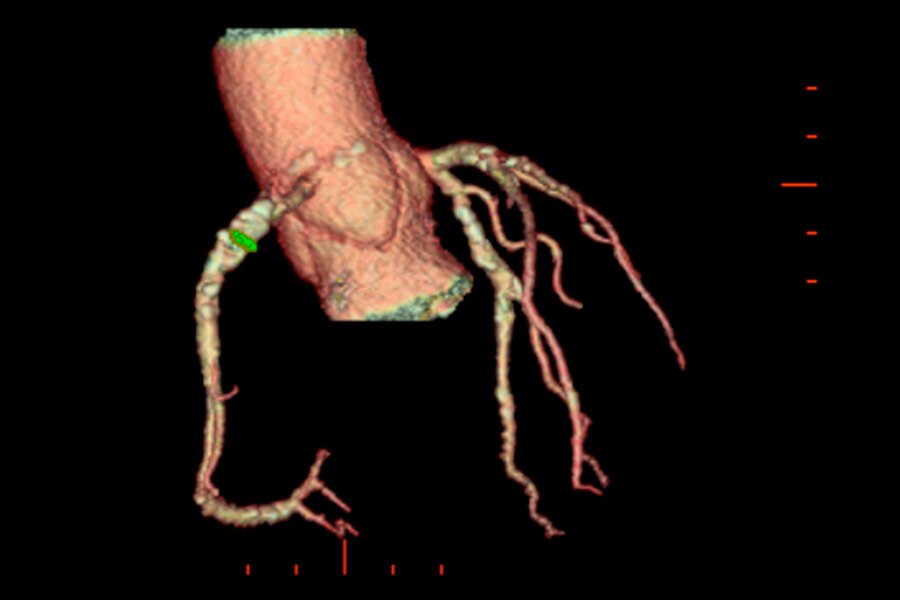

Calcified Plaque on 118 kg patient, 63 BPM, BMI 40.3